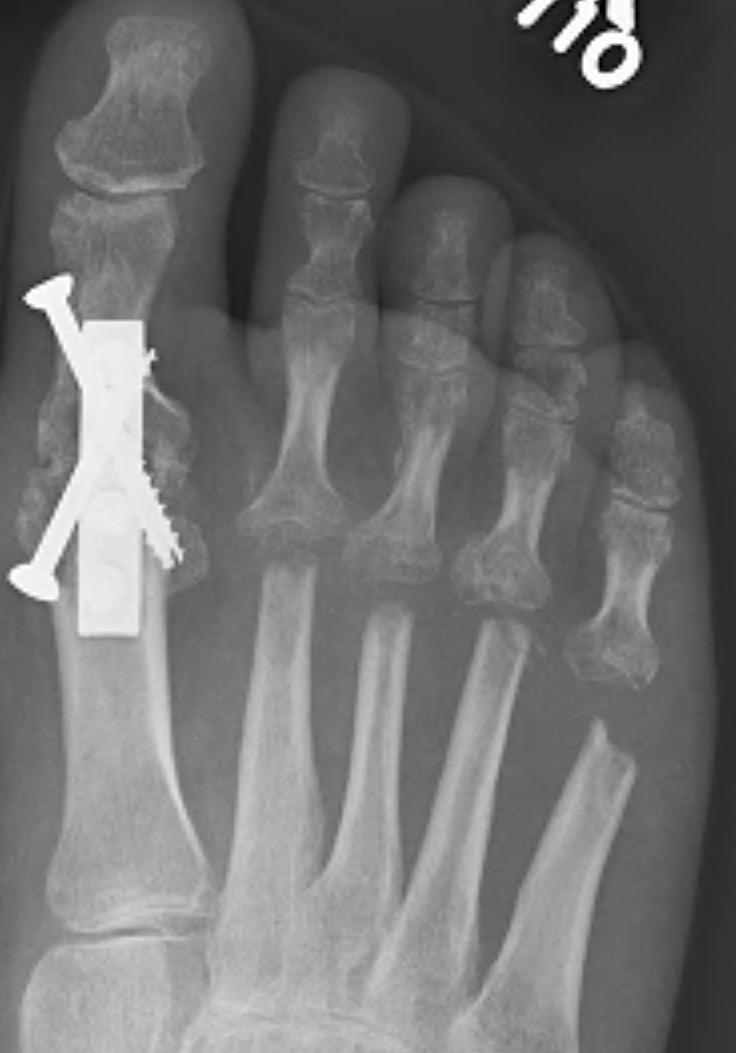

Weil Osteotomy

Technique

Dorsal incision over MTPJ

- web space incisions if doing multiple toes

- mobilize EDL tendons

- capsulotomy to expose MTPJ

Osteotomy

- homan retractors each side of metatarsal

- saw enters at edge of articular surface dorsally

- osteotomy parallel to the floor

- when osteotomy complete the MT head slides back

- needs to slide back at least 5mm

- amputate leading edge of proximal fragment

+/- screw fixion

+/- plantar plate fixation